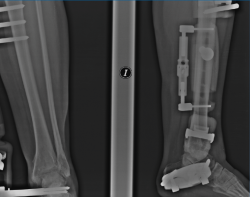

Figura 4. A y B: radiografías anteroposterior y lateral del fijador implantado con la distracción conseguida a nivel articular.

Figura 6. Artrosis postraumática de tobillo tras fractura bimaleolar hace 15 años.

Figura 7. Caso de la Figura 6 con distracción articulada.

Figura 8. Caso de la Figura 6 a los 3 años de la distracción articulada. Obsérvese el mantenimiento del espacio articular a nivel de la articulación del tobillo.